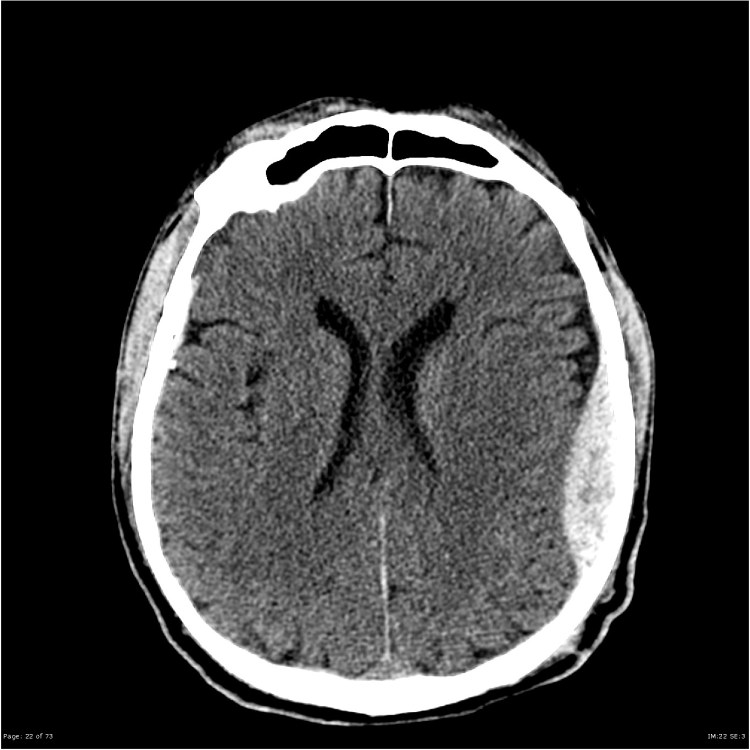

Traumatic head injury is one of the most common traumatic injuries we see in the UK and can have a wide range of presentations. Thankfully Mr Sam Jeffery Consultant Neurosurgeon, is on hand to help us navigate through this topic. Other neurological trauma (spinal trauma) will be covered in another episode.

We take a look at the types of injury, the range of severity of injuries and important elements in immediate management. Critically, we gain expert tips on the assessment of GCS (Glasgow Coma Scale) and Sam highlights how important it is to get this right and to communicate any changes to this.

As always, show notes include the learning areas along with important additional material. Don’t forget to check out our videocast on CT Head imaging in trauma (link below).

ThePTN videocast CT Head here.

Images courtesy of Dr Derek Smith, Radiopaedia.org from the case rID: 36667, Case courtesy of Assoc Prof Frank Gaillard, Radiopaedia.org. From the case rID: 19252